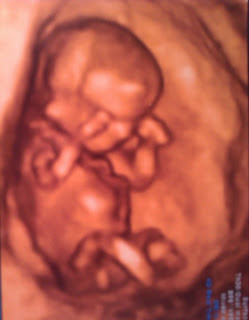

Ma już prawie 18 tygodni.

Wierci się już w brzuszku i zaczyna kopać po żebrach.

Nastusia bardzo się cieszy, że będziemy mieć kolejnego dzidziusia. Kiedy się jej pytamy jak dzidziuś będzie miał na imię i czy będzie to braciszek czy siostrzyczka odpowiada" dzidzia Mikuś" :))